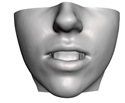

2.6. Textured Output Visualization

3.3. Simulation Error and Performance

4.1. Analysis of Simulation Accuracy

- Chin. Overall, the amount of error at the chin area is very low. This could be explained by the fact that the skin at the chin is very thin, and the coupling to the mandible makes the simulation highly predictive.

- Lips. In other regions, such as the lips, skin slides strongly over the underlying bones and teeth, and the deformation result is more difficult to predict. Overall, we observe higher variability in the error at the lips, and also some patients with higher error.

- Nose. The quality of the prediction of the deformation of the nose varies strongly across patients. In this case, the variability may depend on the type of surgery performed on each patient’s anterior nasal spine. This type of surgery is not easy to identify in the post-operative CBCT image due to the presence of bone grafts or fixation plates.

- Neck. Finally, we observe large error in the neck area (e.g., patients M5 and M8), and specifically at the junction point between the submental area and the neck (“C point” or “cervical point” in cephalometric analysis). This error was accounted for in our quantitative analysis, which negatively biased the overall results. However, this area is not of special interest to orthognathic surgeons. The deformation is known to be produced by a retraction of skin after surgery, but surgeons do not account for this effect during pre-operative planning.